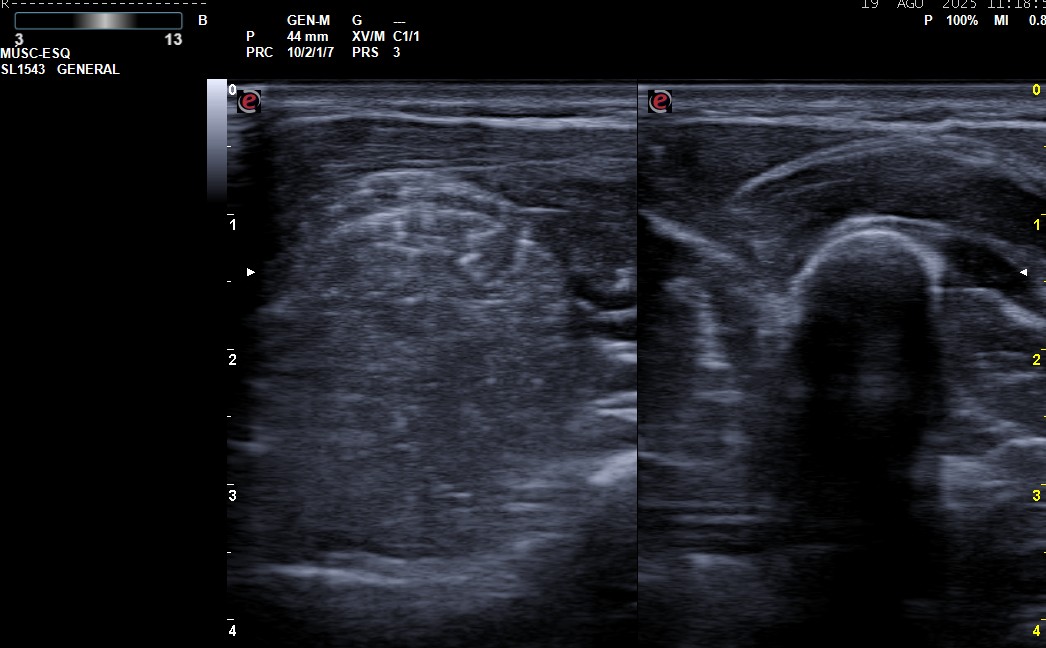

Una mujer de 19 años tenía tumoración blanda en húmero distal derecho. Realizamos una ecografía que mostró una lesión ubicada entre cortical humeral y braquial, hipoecoica, de contornos bien definidos, sin refuerzo posterior con captación Doppler. La RMN evidenció tumor mesenquimal con remodelación ósea, derivándose urgentemente al circuito de tumores músculo-esqueléticos.